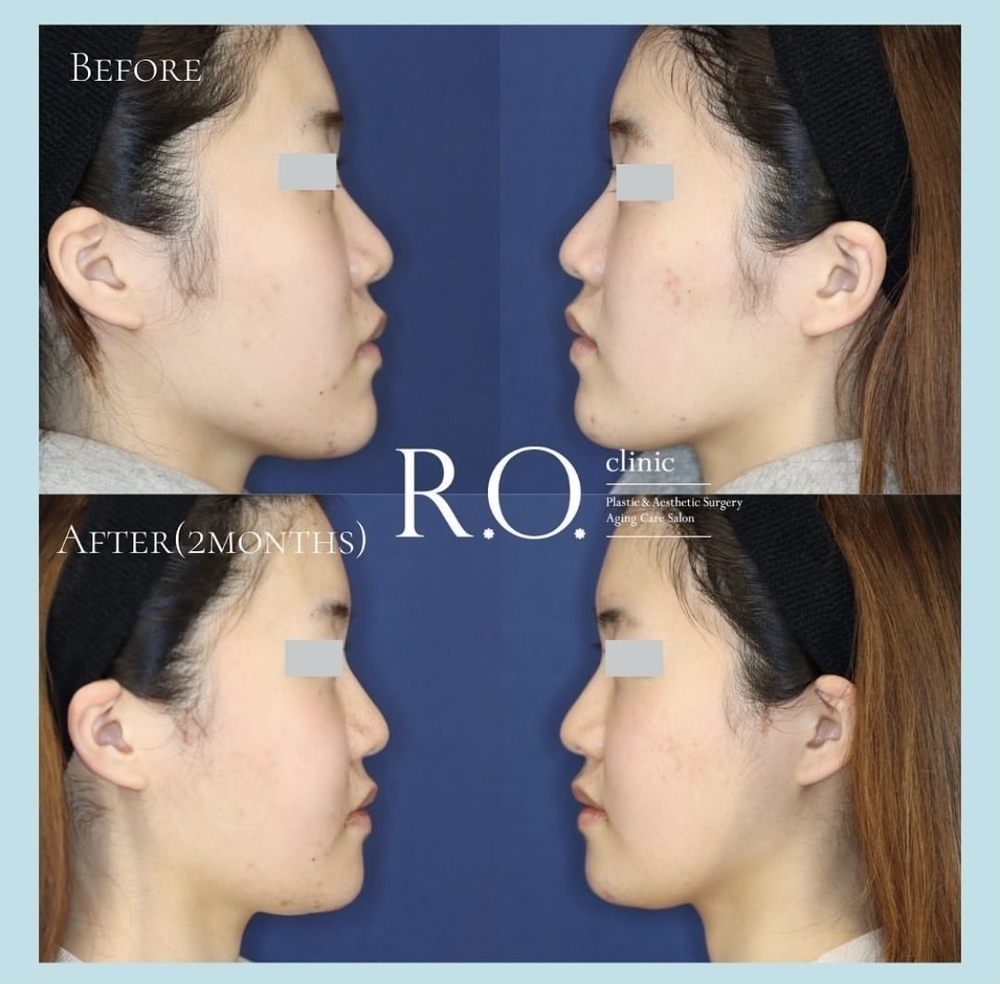

《 注目の症例 》

施術名】頬骨骨切り+あごオトガイ骨切り(中抜き)

【費用】通常価格 2,310,000円

【リスク・副作用】腫れ、内出血、左右差、口の開けにくさ、頬・下あごの知覚障害など

【施術名】下あごオトガイ骨切り(中抜き)

【費用】通常価格 1,100,000円

【リスク・副作用】腫れ、内出血、左右差、あご下のたるみ、下あごの知覚障害など